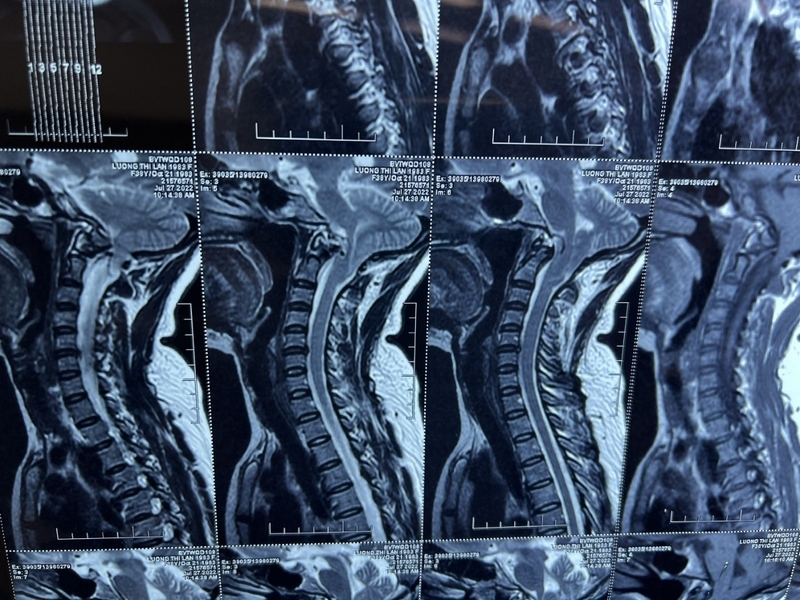

Dị dạng Chiari loại 1 xảy ra trong quá trình phát triển của thai nhi và được đặc trưng bởi sự dịch chuyển vị trí của hạnh nhân tiểu não xuống dưới lỗ chẩm hơn 4mm vào ống sống cổ. Sự di chuyển của hạnh nhân tiểu não có thể cản trở sự lưu thông bình thường của dịch não tủy giữa ống tủy sống và không gian nội sọ.

Để chẩn đoán dị dạng Chiari, bác sĩ có thể yêu cầu bệnh nhân thực hiện nhiều kỹ thuật khác nhau, chẳng hạn như: